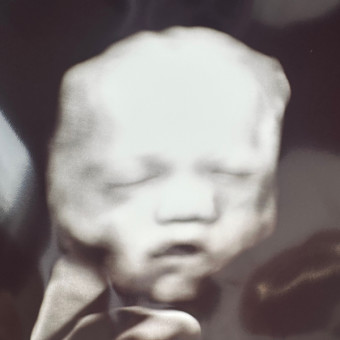

Baby Crofutt

Kate Crofutt & Elisha Crofutt

Freeport, PA

February 2026